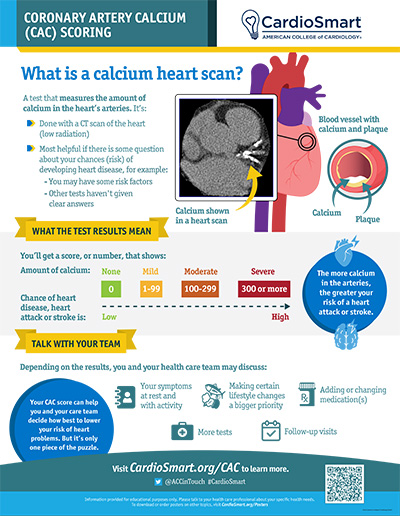

Coronary Artery Calcium (CAC) Scoring – Infographic | CardioSmart

www.cardiosmart.org

www.cardiosmart.org